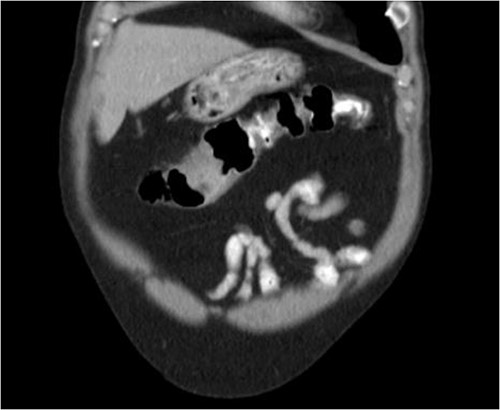

He was then referred to gastroenterology and underwent diagnostic colonoscopy that showed a large polypoid mass in the transverse colon that was partially obstructing. Gastroenterology then obtained a CT scan of the chest, abdomen and pelvis that showed wall thickening of the colon (Figs 1–3). Ultimately when pathology confirmed malignant melanoma, a PET scan was ordered that showed increased uptake at the previously seen and biopsied transverse colon mass (Fig. 4).

Axial CT scan with IV contrast showing thickened transverse colon.